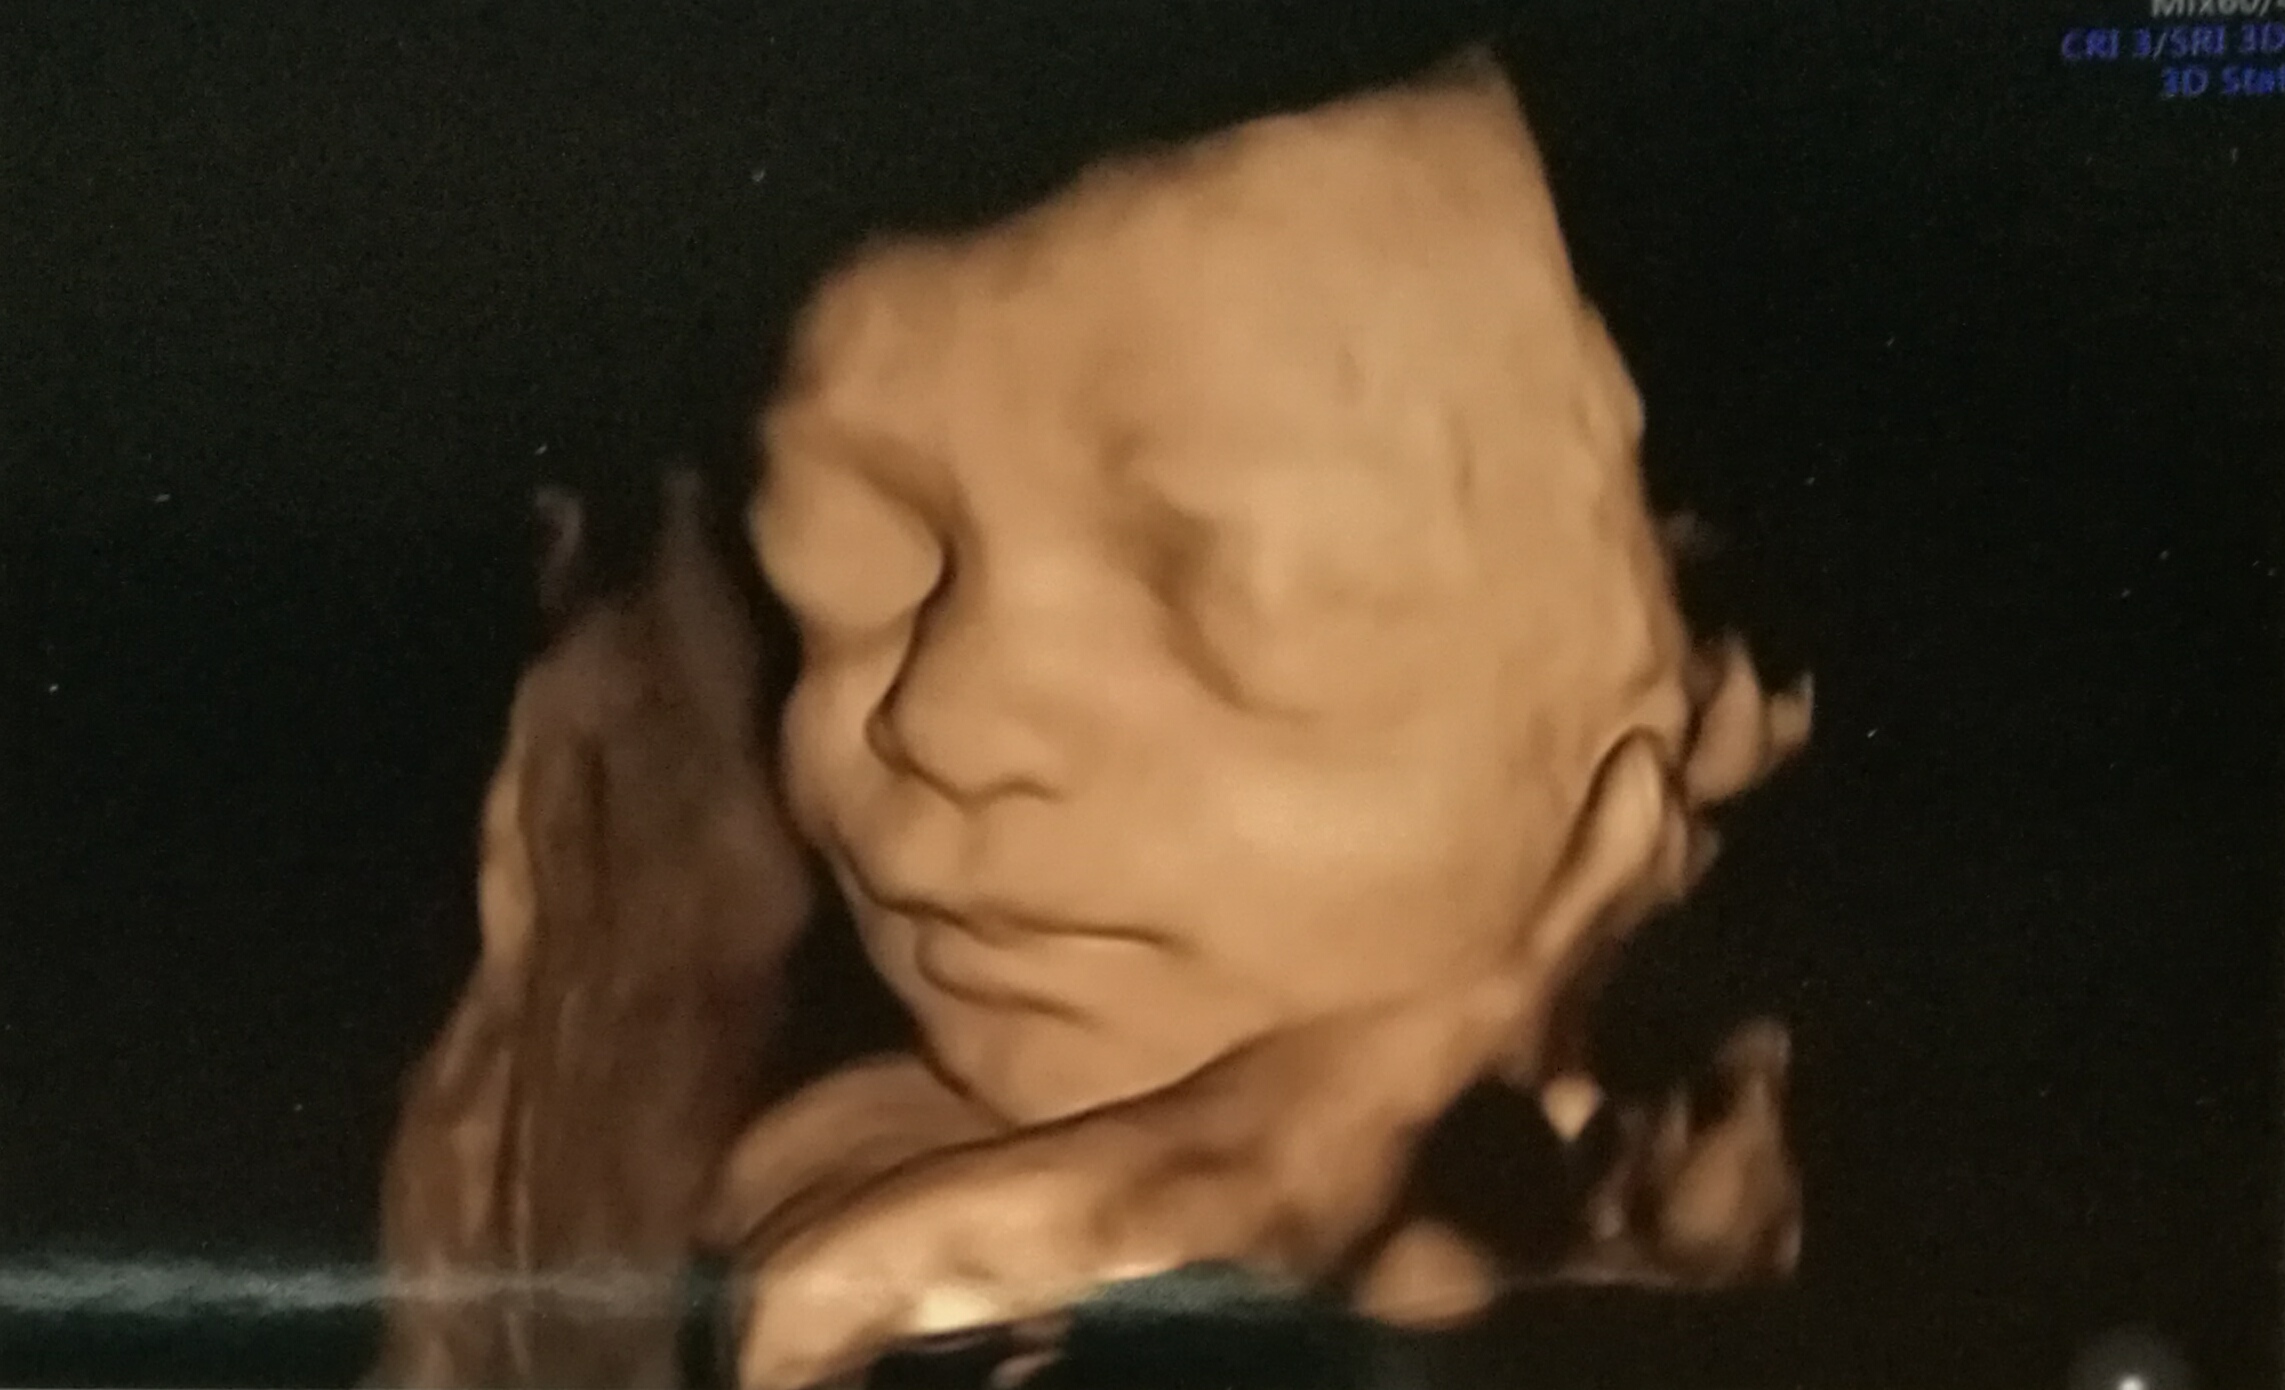

Ya os conté via IG que en esta pequeña familia están a punto de ocurrir grandes cambios. En unos meses (menos de 100 días según la app) en casa habrá más niños que adultos… «la sombra del tercero», como la llama mi amiga Lidia a esas ganas irrefrenables de tener un tercer bebé cuando ya tienes los dos primeros, planeaba con intensidad desde hace tiempo (quizá desde siempre) y finalmente nos dejamos llevar. Resulta que, al menos por ahora, la sombra se ha convertido en un halo de luz, en una nueva brisa mágica que está a punto de hacernos sentir una nueva experiencia maravillosa en nuestras vidas. No hay nada, nada, como dar vida y en estos meses de preparación se siente todo tan intenso.

Imagen de Mamá tiene un Plan